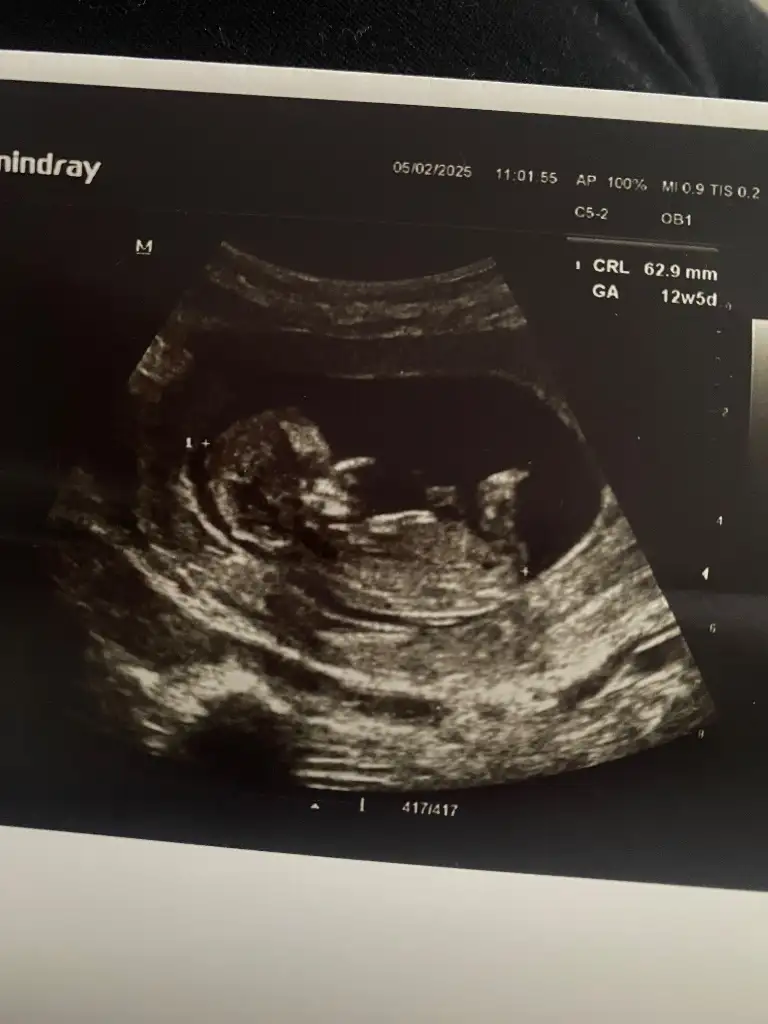

12+5 haftalık sizce cinsiyet nedirBana da erkek gibi geldi. Birde bilimselliği yok tabiki ama kalp atışı hızı falan diyolar sizinkisi kaç acaba cinsiyeti öğrenince de söylerseniz tutup tutmadığını gerçekten merak ediyorum

Erkek gibi ama tabi bilemiyorum12+5 haftalık sizce cinsiyet nedir

Erkek bence kesin hem de benim düşüncem buKızlar selam 13.haftamdayım kesin bir tahmini olan yada anlayan varsa ultrasın fotoğrafı ekleyeceğim sizce cinsiyeti nedir Eki Görüntüle 3539040